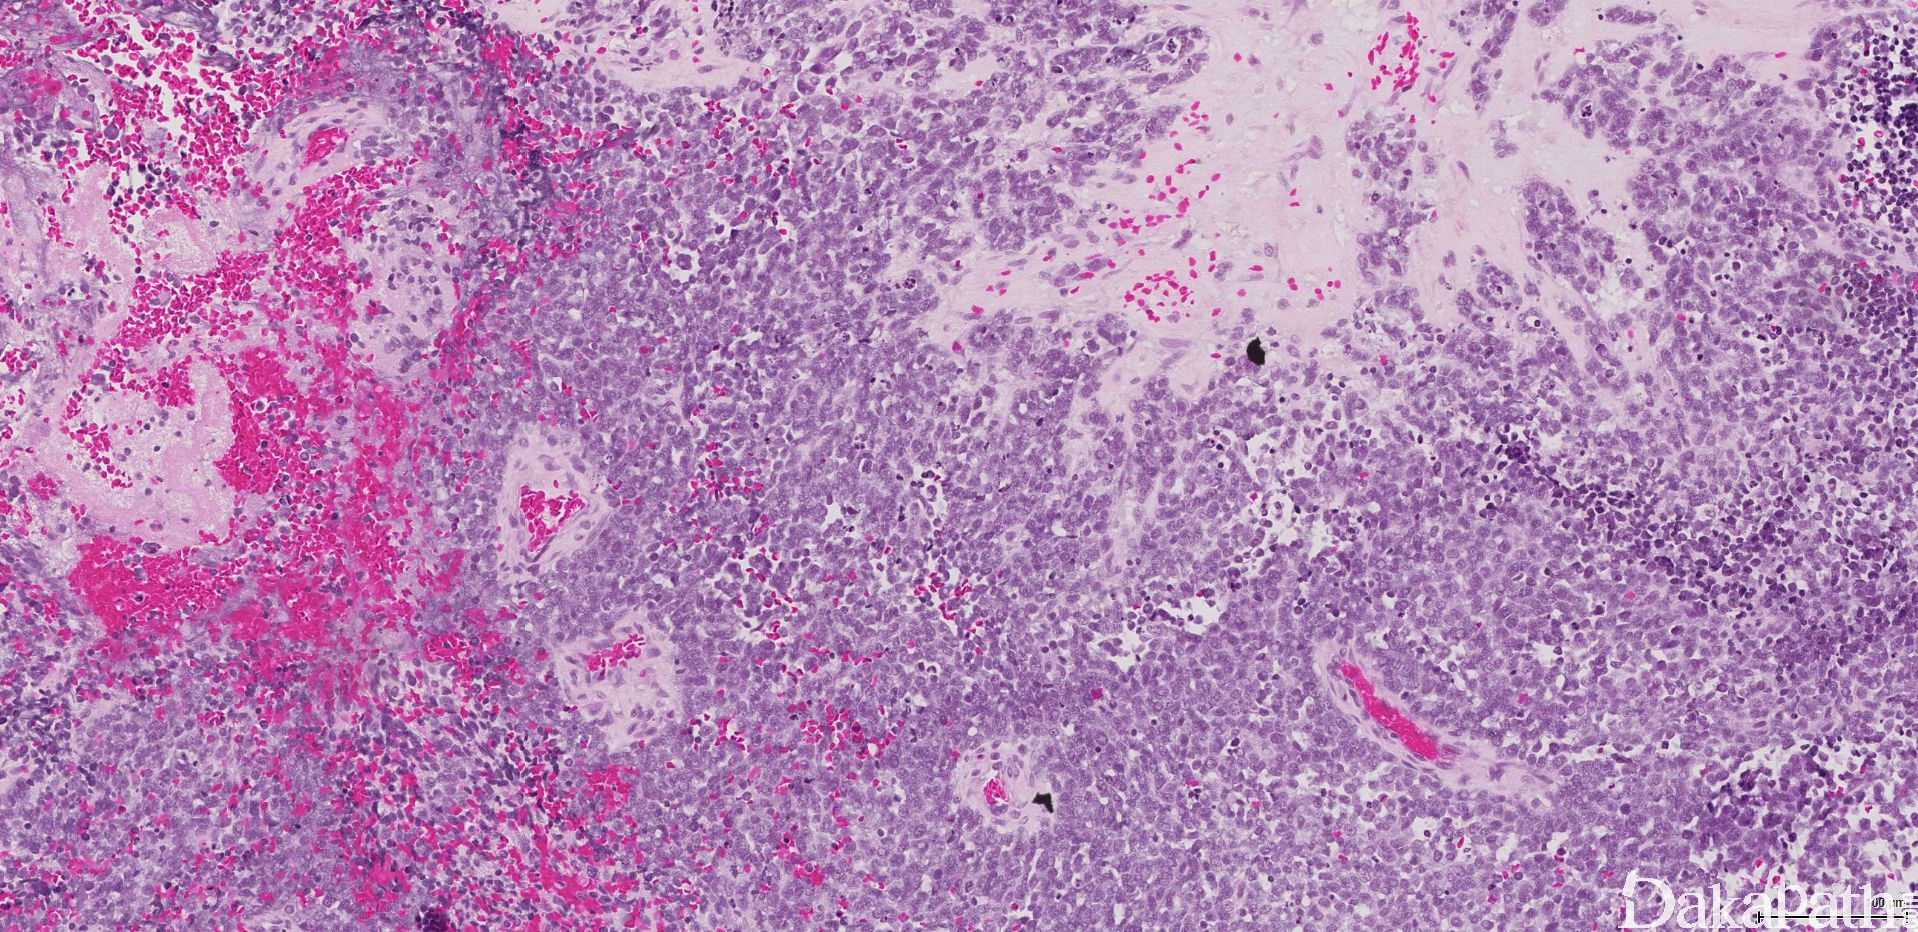

组织学改变基于分化成程度不同而呈不同,原始神经母细胞分叶状排列(不管分级如何)。叶状结构之间富于纤维血管间隔,支持细胞常位于细胞巢周边。

肿瘤细胞呈经典小圆蓝细胞,比成熟淋巴细胞稍微大一些,核浆比高,小而一致的胞核伴细致、椒盐样染色质分布,胞核比较小或缺席。细胞呈合胞体样。可见中央为神经丝状物构成的菊形团(Homer Wright)。

根据分化的程度、神经间质的多少、核分裂像及坏死将肿瘤分成 4 级(Hyams Grading)。1 级:叶状分布,细胞合胞体样,可见神经丝样基质,染色质空泡状,无核分裂及核仁。2 级:神经丝基质变少,核分裂散在。3 级:细胞多形性,真菊形团可见,出现坏死。4 级:显著异型性、核分裂像及坏死。

根据核多形性、核分裂及坏死的有无将肿瘤分为低级别病变(1 级或 2 级)及高级别病变(3 级或 4 级)。核多形性、核分裂及坏死在低级别一般缺如,而在高级别中出现。